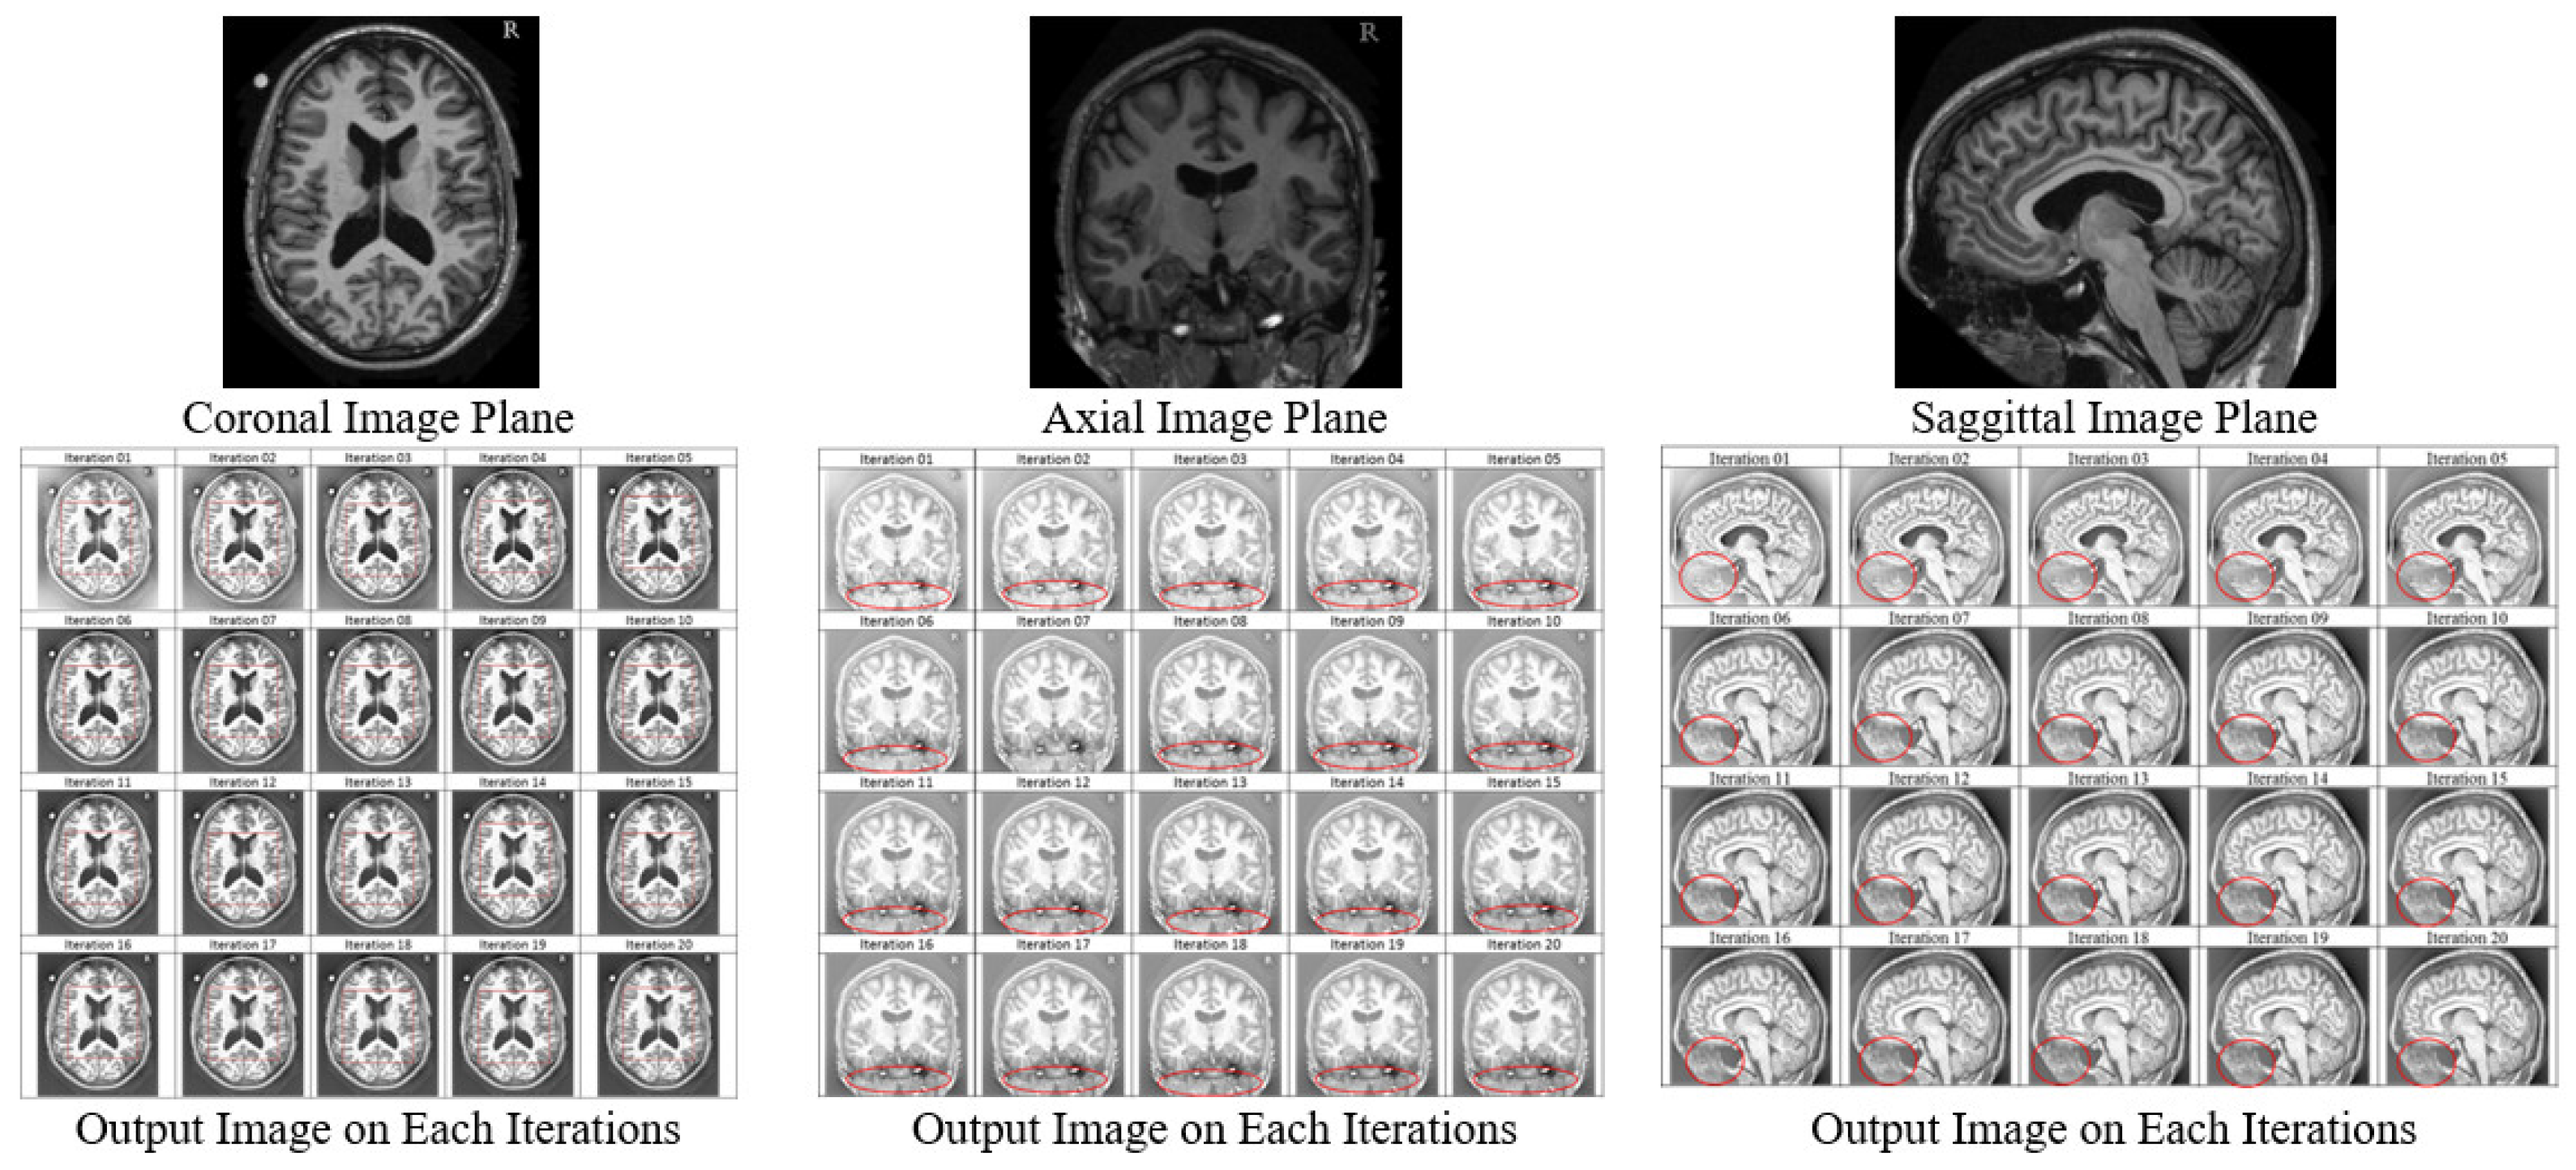

The results showed a similar impact of the McCann Retinex algorithm on the brain MRI; the output of the axial plane images, coronal plane images, and sagittal plane images at each iteration from 1 to 20 are shown in Figure 7.

Figure 7.

Output of Oasis Database Images from Iteration 1 to 20.

The contrast and PSNR at each iteration increased in all three sets of the oasis brain image database as shown in Figure 8. The PSNR in the axial plane images increased from 22.53 dB at iteration 1 to 24.16 dB at iteration 20 (Figure 8a), with an improvement in the PSNR of approximately 1.19 dB at iteration 1 to 2.82 dB at iteration 20 (see Figure 8b), along with an increase in the contrast from 59.81 at iteration 1 to 77.19 at iteration 20 (Figure 8c). The PSNR in the coronal plane images increased from 23.21 dB at iteration 1 to 24.3 dB at iteration 20 (Figure 8d), with an improvement in the PSNR of approximately 2.27 dB at iteration 1 to 3.36 dB at iteration 20 (Figure 8e), along with an increase in contrast from 54.04 at iteration 1 to 69.43 at iteration 20 (Figure 8f). The PSNR in the sagittal plane images increased from 24.03 dB at iteration 1 to 24.89 dB at iteration 20 (Figure 8g), with an improvement in the PSNR of approximately 1.98 dB at iteration 1 to 2.84 dB at iteration 20 (Figure 8h), along with an increase in contrast from 30.06 at iteration 1 to 46.01 at iteration 20 (Figure 8i).